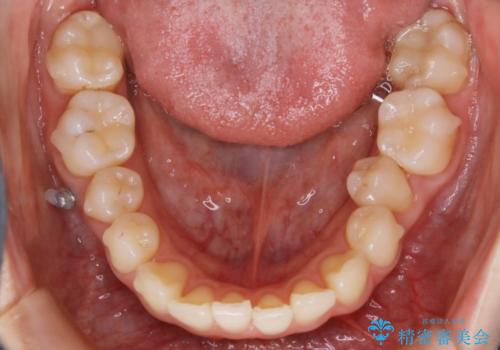

- 笑った時の歯の見え方を治したいとのことで矯正相談にいらっしゃいました。

一見そこまで大きなガタつきはないようにも見えますが、前歯の角度の不揃いや噛み合わせのズレなどから見え方に影響が出てしまっていました。

抜歯は全く必要のないレベルのガタつきだったため、マイクロインプラントを用いて歯全体を後方に移動させていくことできれいな歯並びを獲得することができました。